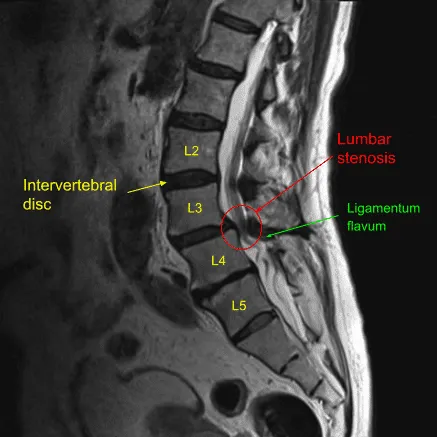

Resonancia magnética de la columna lumbar en la sección sagital que muestra hernia discal L4-L5.

La columna lumbar está formada por cinco vértebras (L1-L5) separadas por discos intervertebrales. Los discos actúan como amortiguadores y permiten el movimiento entre vértebras. La médula espinal atraviesa el canal espinal y las raíces nerviosas salen por aberturas llamadas forámenes. Estos nervios controlan la sensibilidad y el movimiento en las piernas, y cuando se comprimen por una hernia o un disco abultado, pueden provocar dolor, entumecimiento y debilidad en la zona afectada.